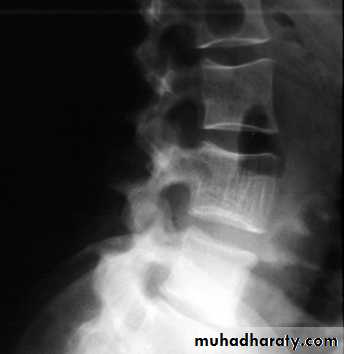

Cavernous Haemangioma